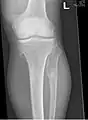

It is characterized by the growth of cartilage-capped benign bone tumours around areas of active bone growth, particularly the metaphysis of the long bones. Typically five or six exostoses are found in upper and lower limbs. Image depicts adult regrowth after knee replacement.

The diagnosis of HMO is based upon establishing an accurate correlation between the above-mentioned clinical features and the characteristic radiographic features. Family history can provide an important clue to the diagnosis. This is supplemented by testing for the two genes in which pathogenic variants are known to cause HMO namely EXT1 and EXT2. A combination of sequence analysis and deletion analysis of the entire coding regions of both EXT1 and EXT2 detects pathogenic variants in 70–95% of affected individuals.[3][4] The hallmark of radiographic diagnosis is the presence of osteochondromas at the metaphyseal ends of long bones in which the cortex and medulla of the osteochondroma represent a continuous extension of the host bone. This is readily demonstrable in radiographs of the knees.[3][1]

multiple osteochondromas around the knee